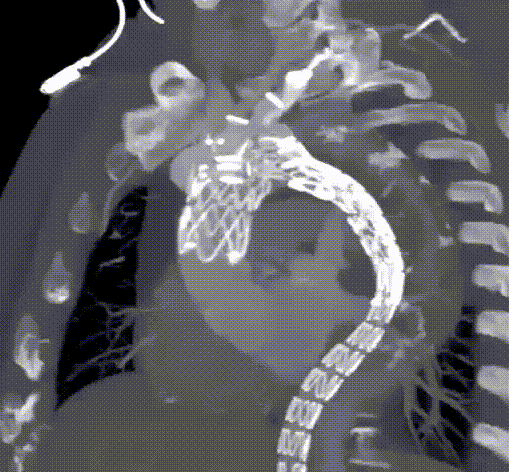

新型三分支胸主动脉覆膜支架示意图

核心设计创新

★ 主体支架(Mainbody)

无名动脉外分支与双内嵌分支:主体支架由1个一体式无名动脉外分支与2个内嵌分支组成(分别对应左颈总动脉LCCA和左锁骨下动脉LSA),内嵌分支结合顺行与逆行技术,减少内漏风险(尤其是III型)。

下沉区(Sinking Zone):预留空间便于LCCA和LSA分支支架导入和展开,并适应不同LCCA与LSA间距的解剖变异。

血流动力学优化:通过内嵌分支通道维持头臂干(IA)顺行血流,降低剪切应力,减少术后并发症。